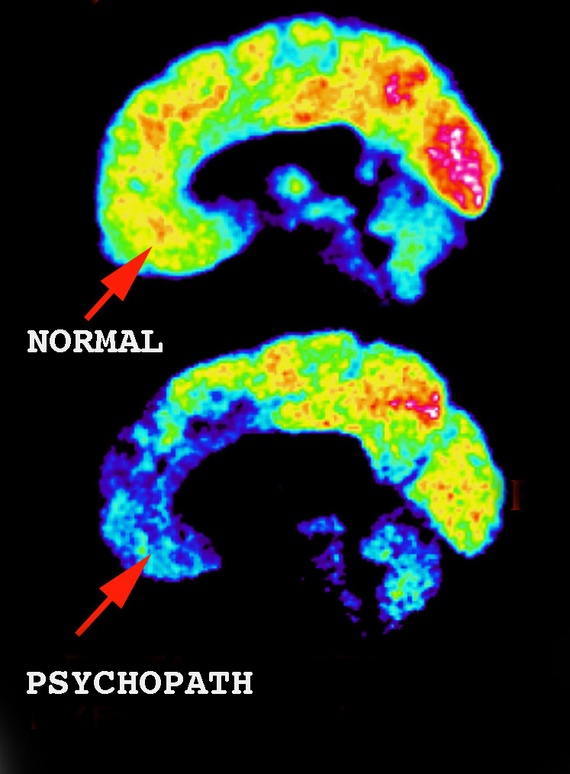

När han fördjupade sig i forskningen och utförde hjärnröntgen på psykopater samtidigt som han utsatte dem för bilder som hos normala människor skapar starka känslor så reagerade inte psykopaternas hjärnor. Frontalloben och temporalloberna är på något sätt skadade hos psykopater vilket gör att de inte har förmåga att känna vare sig EMAPTI, SKAM eller SKULD. En bild med en hemsk våldsscen och en smörgås ger skrämmande nog samma reaktion.